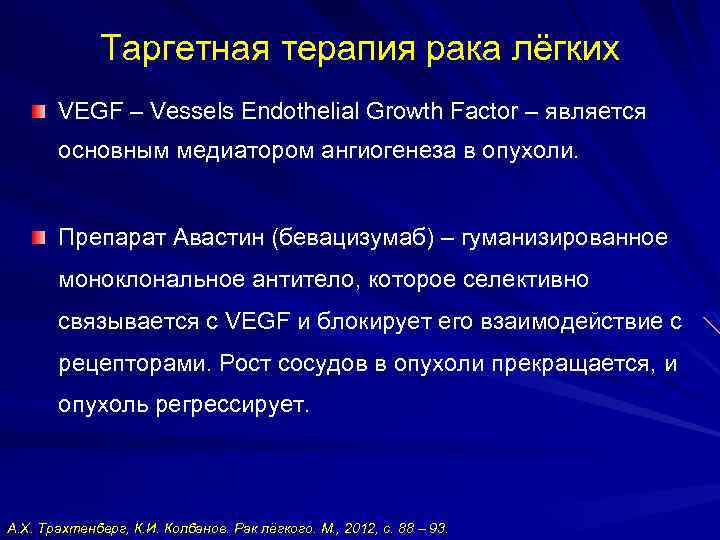

Таргетная терапия РМЖ: Инновации в лечении